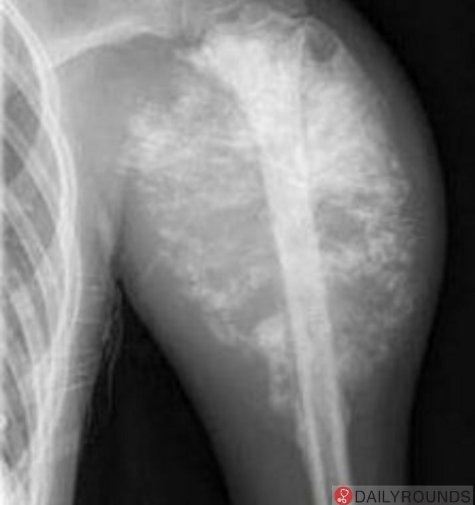

The X-ray showing periosteal lifting and _____ appearance is suggestive of osteosarcoma